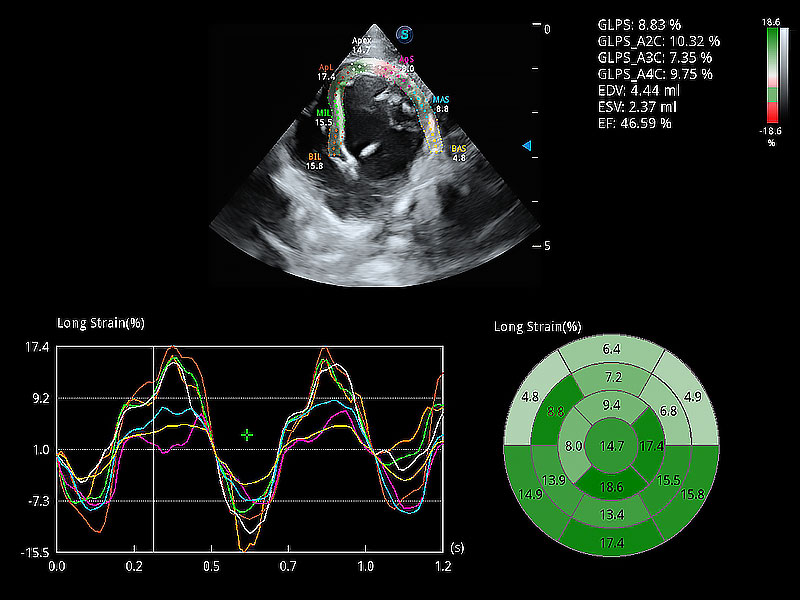

通過心肌識別技術(shù)與二維斑點追蹤技術(shù)相結(jié)合,對心臟的超聲圖像進行量化分析。計算心肌17個節(jié)段的應(yīng)變、應(yīng)變率、速度、位移等,并通過牛眼圖的形式進行呈現(xiàn)。